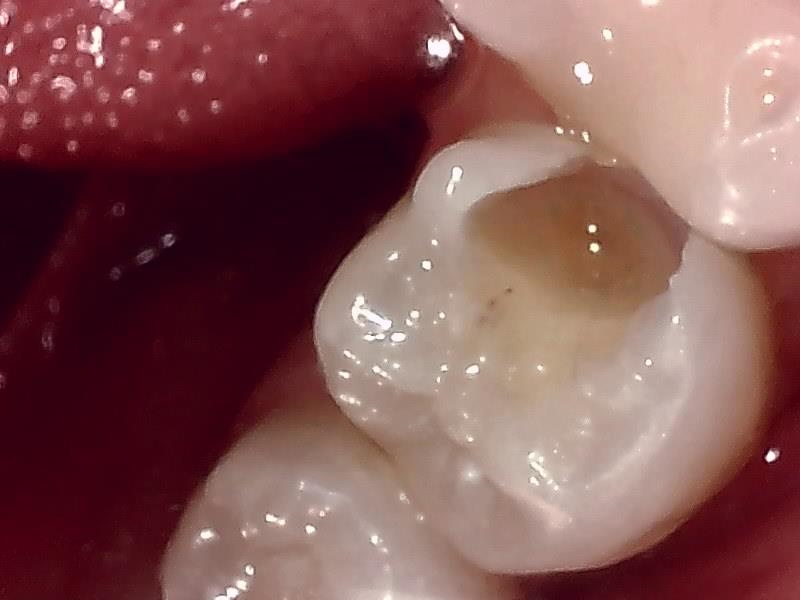

保険レジン充填の症例(奥歯)

Before

After

| 主訴 | 奥歯の虫歯を保険診療の範囲内で、かつ白く自然に治したい。 |

|---|---|

| 年齢・性別 | 30代 女性 |

| 治療方法 | コンポジットレジン充填 |

| 費用 | 保険診療 |

| 備考 | レジンはプラスチックを主成分とするため、金属(メタル)やセラミックに比べると強度が低いです。奥歯でグッと噛みしめる力が強い方や、歯ぎしりのある方は、稀に欠けたり割れたりすることがあります。 |